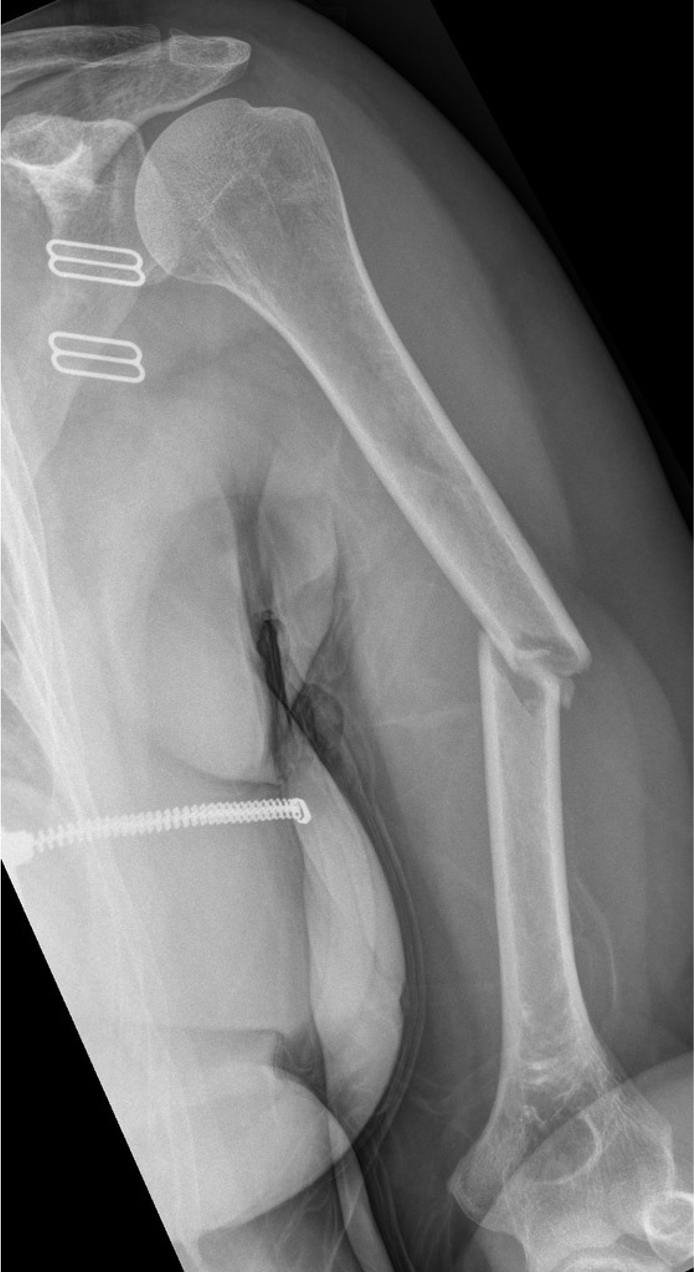

A 22 year old woman presents to her local hospital following an electric scooter accident. She presents with significant pain and weakness, limiting movement at the shoulder and elbow.

radiolucent, oblique fracture of the shaft of the left humerus, with medial displacement